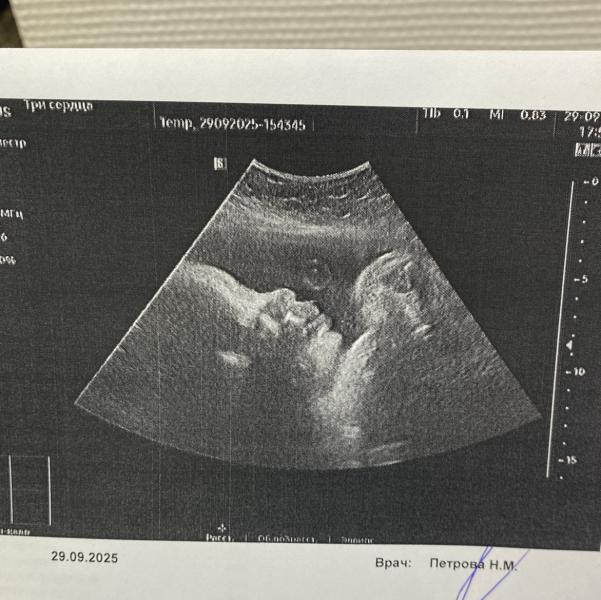

Ну сладкий, лежит, будто пузыри пускает

Почти копия старшего в профиль 🤭

Шейка вообще 41мм